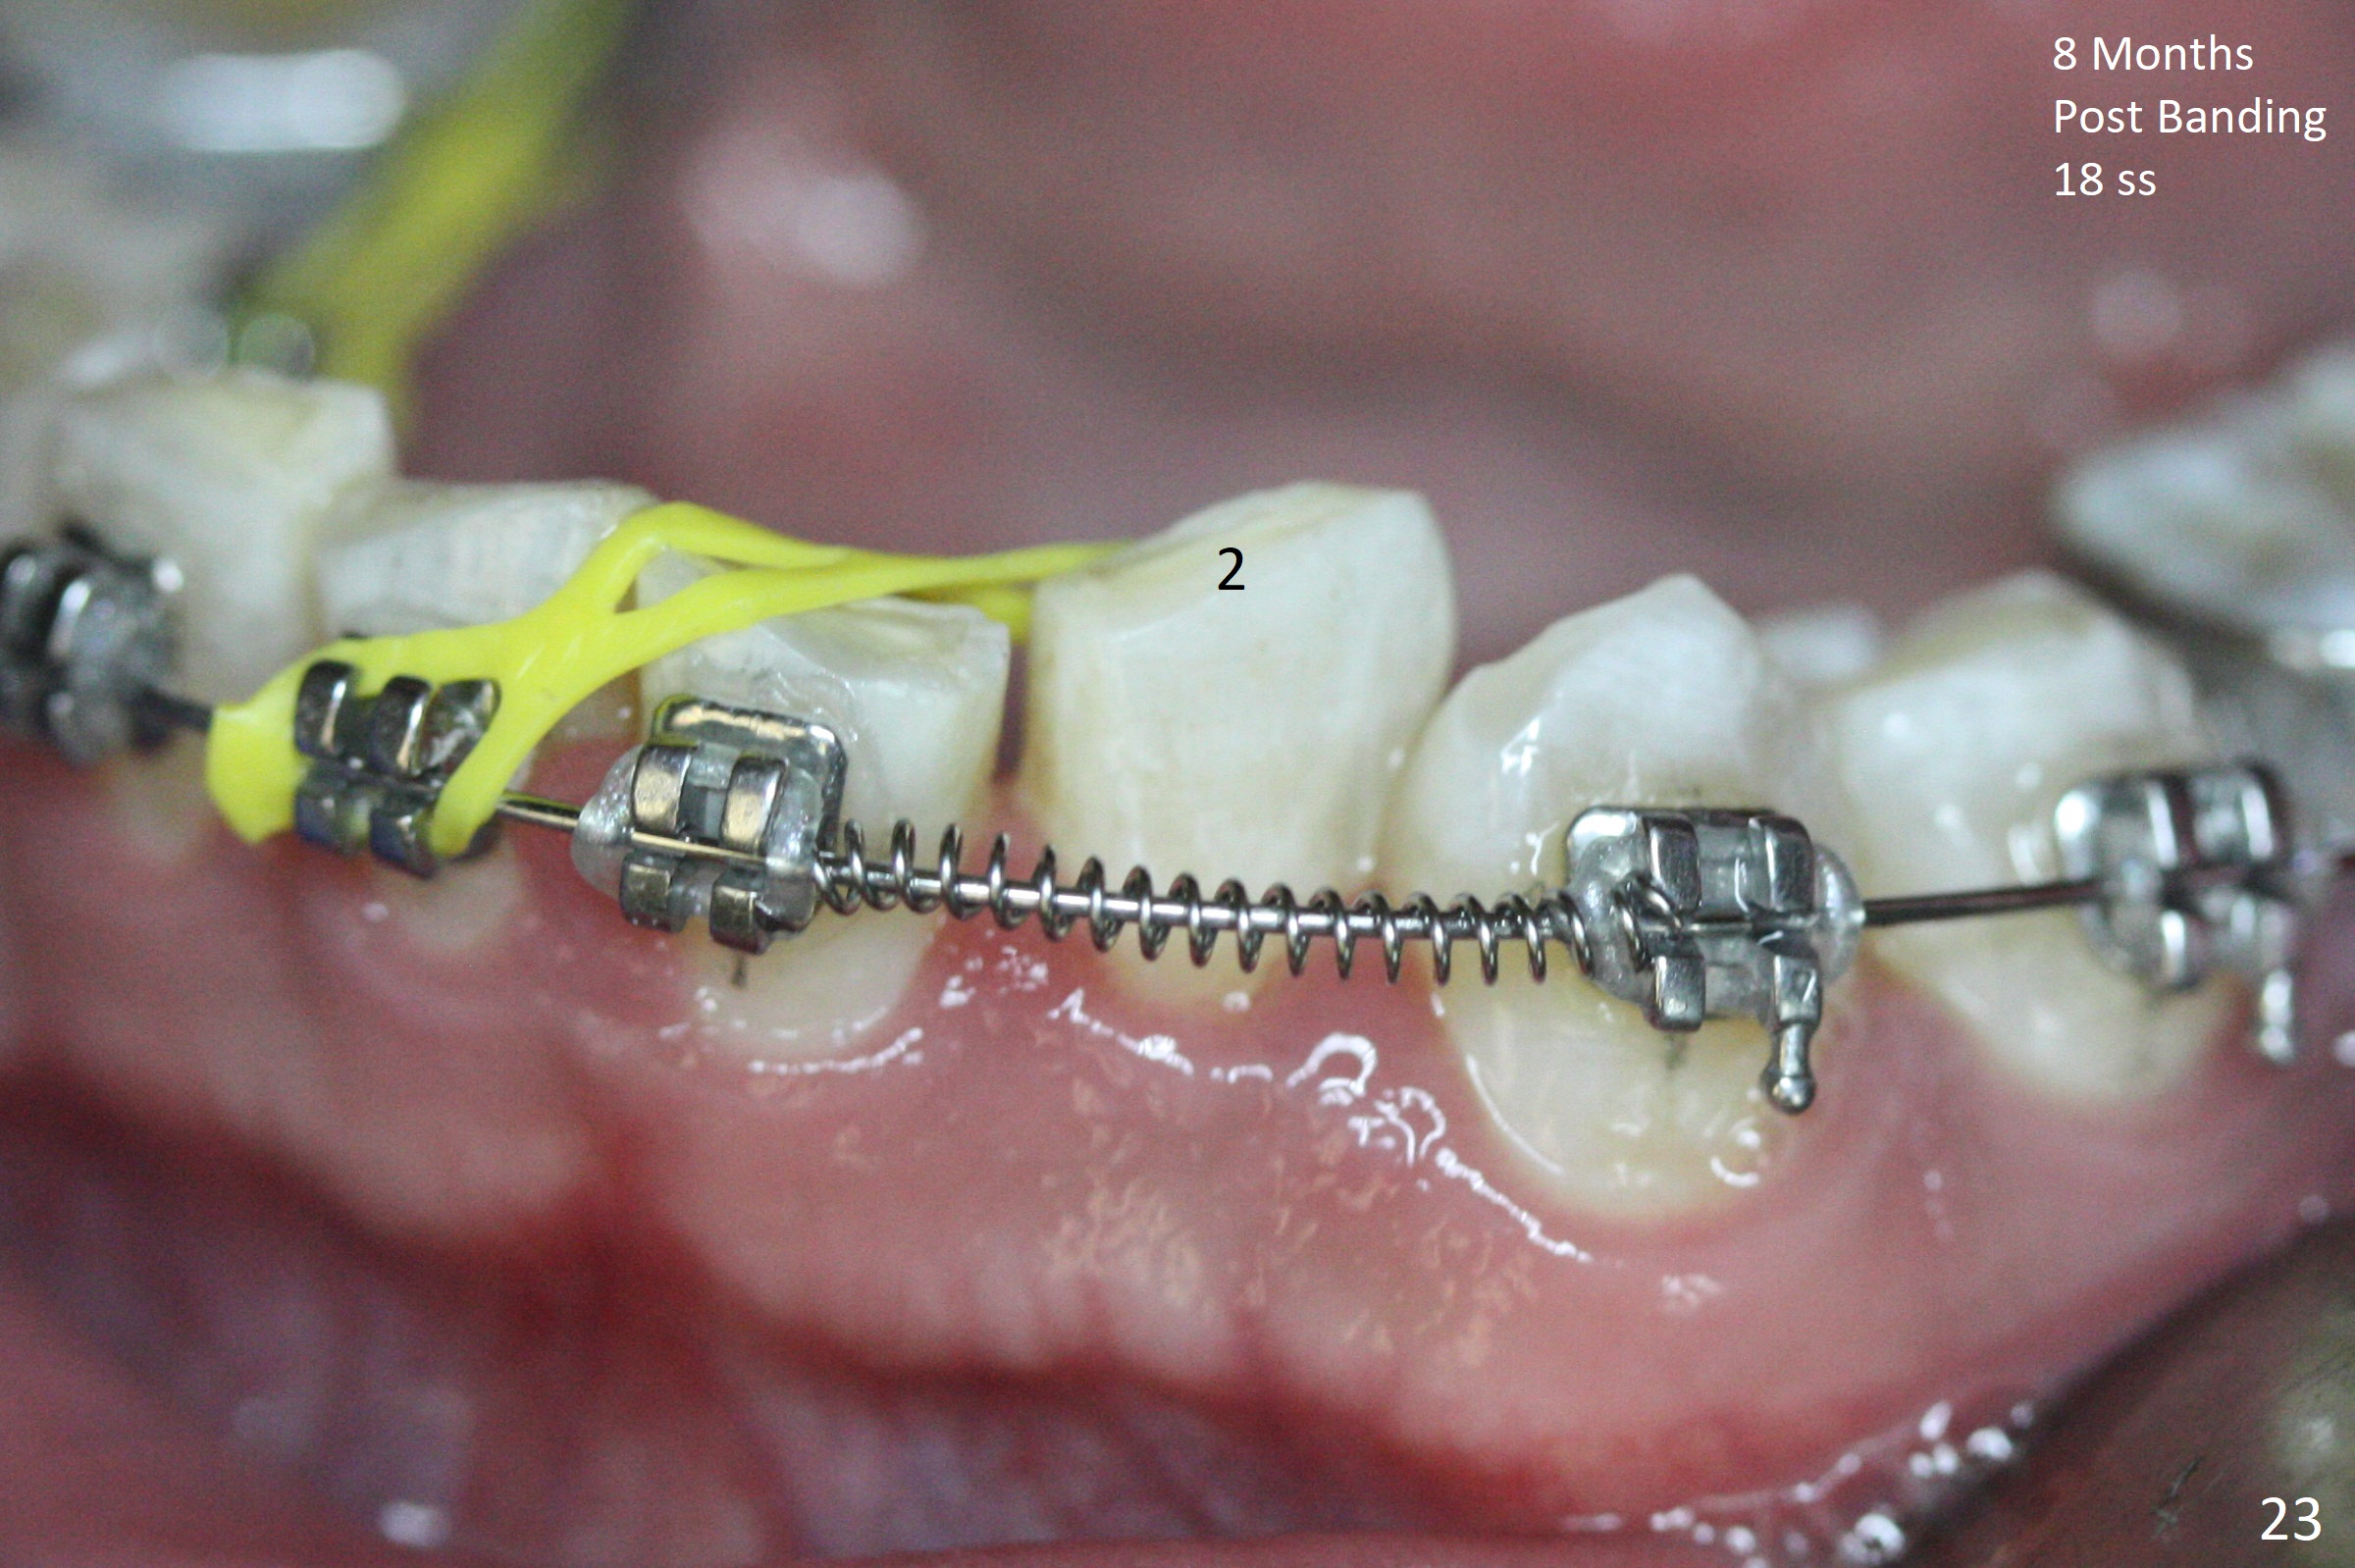

Severe crowding (Fig.1-7) appears to be alleviated especially 2 months after UR5 extraction. Diastemata seem to form mesial and distal to UR2 (Fig.8). Because of severe wear at UR3 (Fig.6), there is no bracket placement differential around it (Fig.8 (14 niti wire)). Lower bands and brackets are placed a week later (Fig.9-11). Because of tight space between LR4 and the opposing tooth (Fig.10), band adhesive is applied to L7 occlusal surface to open the bite (Fig.9). There is an abrupt kink of 12 niti wire between LL4 and 6 (Fig.11). The latter does not improve much in a month; the wires remain the same (Fig.12). For LL2, LR4 has been retracted for ~ 1 month (Fig.13). There is mild tension when 18 ss wire is inserted between LL4 and 6 five point five months post banding (Fig.14). UR4 has been distalized for a month using buccal power chains x3 resulting in rotation; to counter the rotation, a lingual button is placed with power chain x3 lingual and x2 buccal (Fig.15). With space gaining, it is time to finish definitive filling (Fig.16 *). Next visit check midlines, overjet, interdigitation, and molar classification. R4s distalize, but associate with rotation because of power chains buccal and lingual 8 months post banding (Fig.17,18). With the use of the same wires, power chains are applied lingual to continue distalization and rotation correction (Fig.20,21). Lingual buttons are placed at L2s buccalization (Fig.19) and mesialization (Fig.22,23). It appears that space should be created distal to LR3. That is that the lower anterior teeth should be shifted to the right, although it may be not appropriate for the midline.